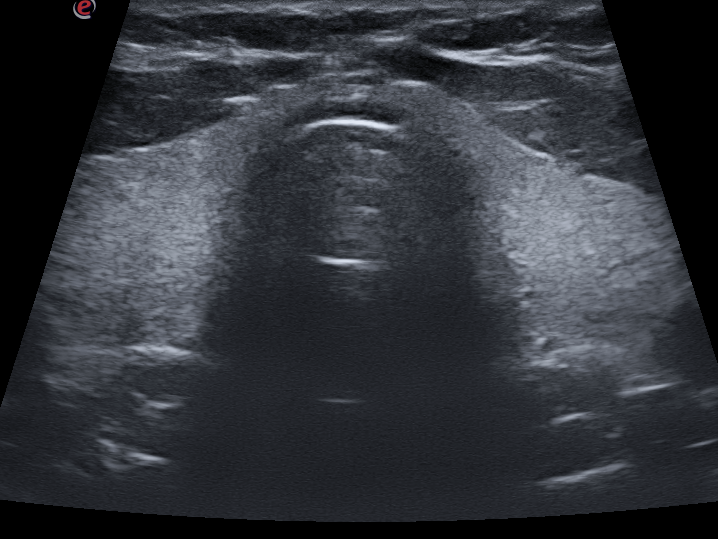

Thyroid

Thyroid: To evaluate the size of the thyroid as well as any masses or abnormal growths in the thyroid. Inflammation of the thyroid and lymph nodes in the neck can also be detected.